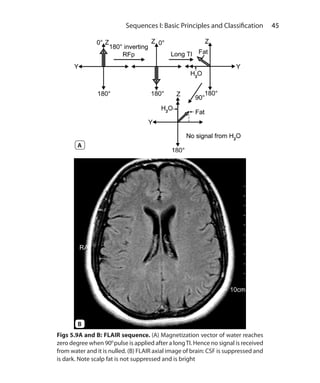

When 90 degree pulse is applied at short TI, LM for all or virtually all

tissues is still on negative side.The tissues with shortT1 have near zero

magnetization, so don’t have much signal. Most pathologic tissues

have increasedT1 as well asT2. Moderately highTE used in STIR allows